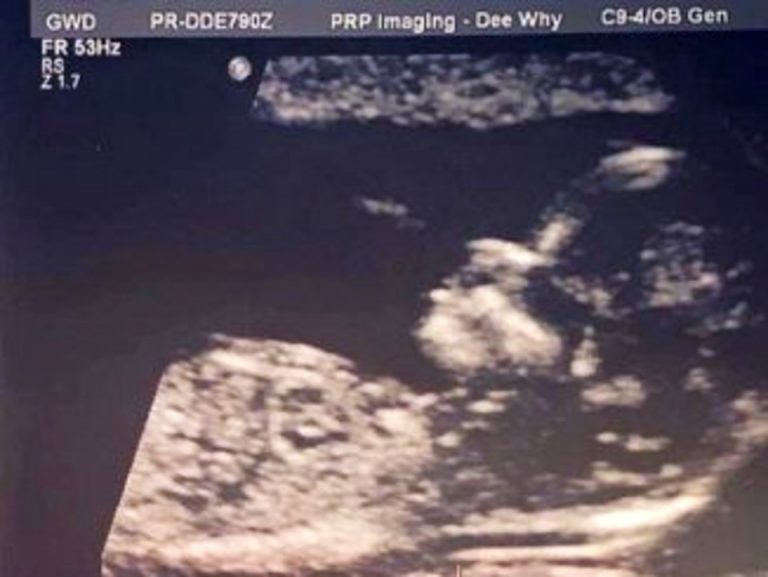

An ultrasound X-ray revealed that babies have hair just a few weeks after conception, although it usually takes a year or two for infants to develop hair extensions.

Some babies may not have lush locks on their heads for months or even years. Little Alexis’ hair was already visible in the womb.

Alexis Bartlett, an adorable six-month-old baby, has so much hair that even though her parents in Sydney saw the signs on an ultrasound, they were shocked at her birth.

“The ultrasound even revealed that she was going to be hairy, which was a clear sign that she was going to mimic me in some ways.